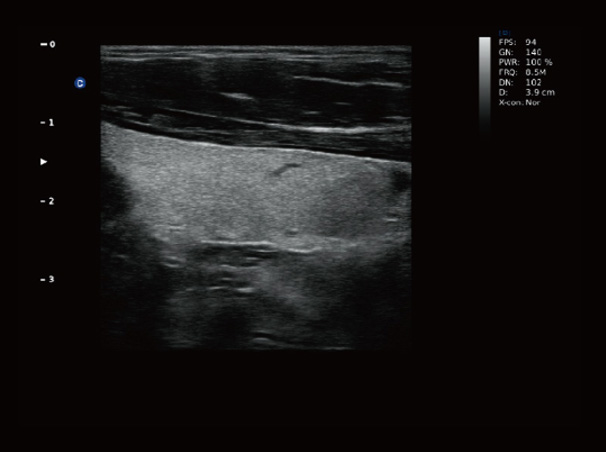

Chison Qbit 3 Color Doppler Digital Ultrasound Machine

Chison Qbit 3 A Slim Console Color Doppler System, Offers Ideal Patient Care With Its Easy Mobility, Smart Features, Significant Performance And Streamlined Workflow, To Strengthen The Clinical Confidence And Speed The Diagnostic Decision.

QBit 3 Slim.Smart.Significant.Streamlined

Chison Qbit 3 Ultrasound Machine

Chison QBit-3 Ultrasound Machine System, Offers Ideal Patient Care With Its Easy Mobility, Smart Features, Significant Performance And Streamlined Workflow, To Strengthen The Clinical Confidence And Speed The Diagnostic Decision.